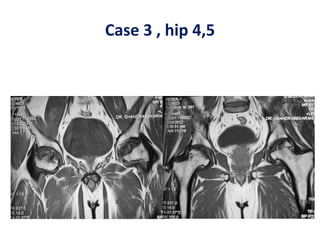

Case 3 , hip 4,5

Case 3 ,hip 4,5 Pre op Post op

Case 3 ,hip 4,5